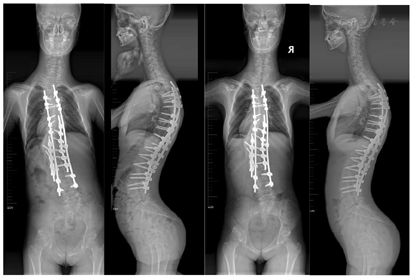

后入路胸腰椎融合术以及T7~L2的8节段的Smith-Peterson截骨术(Smith-Peterson osteotomy,SPO)进行脊柱矫形,限制脊柱侧弯的进行性加重,防止肺功能障碍的发生。术后予抗感染、止痛、消肿补液对症支持治疗,患者恢复良好,术后X线显示脊柱矫形良好。

患者术后恢复良好,无相关并发症,无特殊不适,术后X线提示脊柱矫形效果令人满意。分别于术后6个月及1年对患者进行随访,X线示患者内固定在位,矫形良好,未见螺钉松动、断棒等并发症。

患者6岁时出现跛行步态,X线显示右下肢缩短2 cm,7岁时发现胸腰背部不对称畸形,曾多方就诊,全基因型筛查初步考虑"变形综合征",至当地医院支具保守治疗。近4年来胸腰背部不对称进行性加重,遂至医院就诊。立位全脊柱正侧位片示脊柱侧弯,收住入院治疗。为改善患者畸形体态,防止脊柱侧弯的进行性加重,以及防止脊柱侧弯并发症的发生,于辅助检查完善后行后入路胸腰椎融合术以及T7~L2的8节段的Smith-Peterson截骨术(Smith-Peterson osteotomy,SPO)进行脊柱矫形。手术顺利,术后给予抗感染、止痛、消肿补液对症支持治疗,患者恢复良好,无相关并发症发生,术后X线提示脊柱矫形良好,内固定在位,未见明显松脱及折断征象(图4)。术后6个月以及1年的随访全脊柱X线示患者内固定在位,矫形良好,未出现螺钉松动、近端交界性后凸等并发症(图5)。